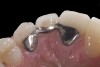

(5.) Double-wing metal resin-bonded bridge replacing lateral incisor (lingual view).

Figure 5

A 14-year-old patient presented to the office with his mother (Figure 1). His chief complaint involved the large spaces between the teeth created by his missing right maxillary lateral incisor and his small left maxillary lateral incisor. He desired to replace the missing tooth with an implant and create a beautiful smile. Upon examination, he was found to have a class I canine and molar relationship, but because he had a tooth size/arch size discrepancy and space distal to the right central incisor, the remaining incisors had drifted to the right. The left maxillary lateral incisor was peg-shaped and in a cross bite position. Studies have shown a clear association between congenitally missing teeth and reduced tooth size.59-62 Because he was only 14-years-old at the time and could not have implants placed until the cessation of growth (somewhere in the vicinity of 22 years old), he was sent to the orthodontist for alignment of the teeth.16,17 After 2 years of orthodontics, the appliances were removed, and his tooth coloration was improved using carbamide peroxide bleaching (Figure 2). Because some form of provisional needed to be placed until he was finished growing, a double-wing metal resin-bonded bridge was chosen. As discussed earlier, this is the ideal transitional prosthesis for patients that have congenitally missing maxillary lateral incisors. The benefits of this type of prosthesis include its ability to be removed and rebonded during the surgical phase of treatment and its ability to retain the roots in their proper position after orthodontic treatment.16 The final plan for the patient was to increase the width of the central and the maxillary left lateral incisor, utilizing porcelain laminate veneers to achieve the appropriate width/length ratio of 80%. A wax-up was created to idealize tooth size, a putty matrix was made from the wax-up to facilitate bonding of the incisors, and a non-precious, double-wing metal resin-bonded bridge was fabricated for lateral incisor replacement. Once the teeth were bonded to ideal size, the “Maryland Bridge” was fabricated from a polyvinyl arch impression with the newly bonded teeth (Figure 3). The metal frame was cast from a non-precious alloy to allow for fabrication of a very thin frame and to create a better surface for bonding. After sandblasting the internal aspect of the frame with CoJet™ silica (3M ESPE), accomplishing salinization, and executing cementation with a dual-cure resin cement, a fairly good adhesion to the frame was anticipated.29 The enamel surface was etched with phosphoric acid for 30 seconds, the primer (Single Bond Plus, 3M ESPE) was applied to both the internal surface of the sandblasted framework and the etched enamel, and the bridge was cemented with RelyX™ ARC (3M Espe) dual-cured resin cement (Figure 4 and Figure 5).